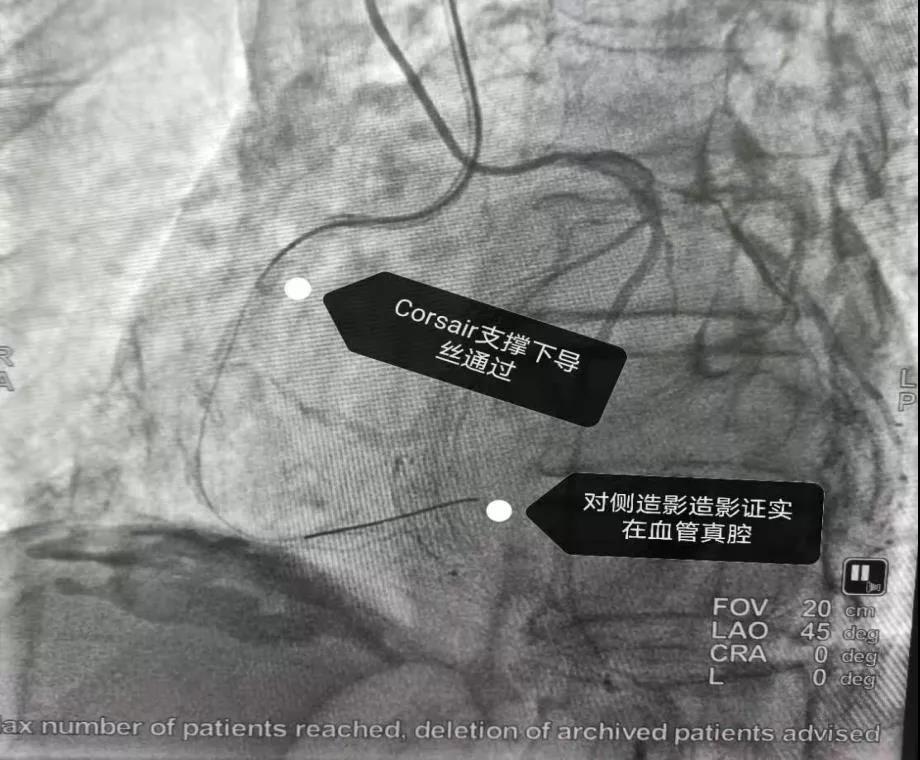

对侧造影能看到右冠状动脉闭塞段以远了

2.jpg

3.jpg